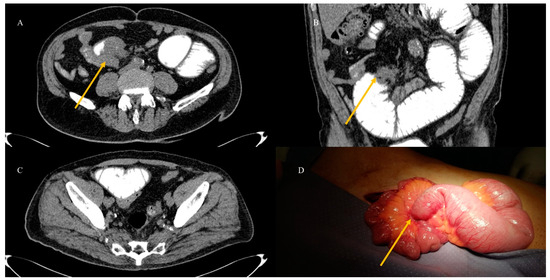

- Tuca, A.; Guell, E.; Martinez-Losada, E.; Codorniu, N. Malignant bowel obstruction in advanced cancer patients: Epidemiology, management, and factors influencing spontaneous resolution. Cancer Manag. Res. 2012, 4, 159–169. [Google Scholar] [CrossRef]

- Nelms, D.W.; Kann, B.R. Imaging modalities for evaluation of intestinal obstruction. Clin. Colon. Rectal Surg. 2021, 34, 205–218. [Google Scholar] [CrossRef]

- Paulson, E.K.; Thompson, W.M. Review of small-bowel obstruction: The diagnosis and when to worry. Radiology 2015, 275, 332–342. [Google Scholar] [CrossRef] [PubMed]